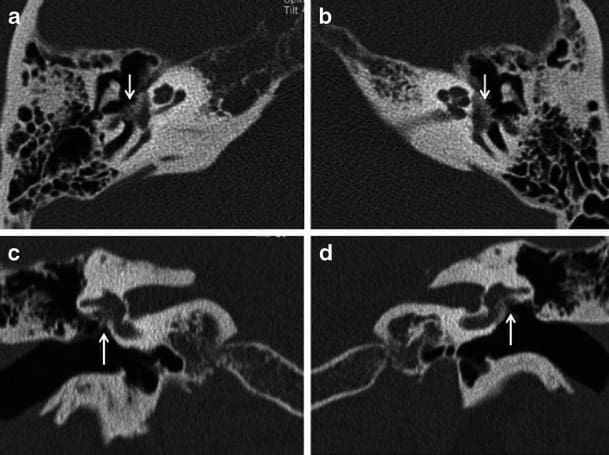

Выявить заболевание можно на основании данных аудиограммы пациента. Также дополнительную информацию о степени повреждения слуховых косточек могут дать такие исследования как импедансометрия, компьютерная томография височных костей.